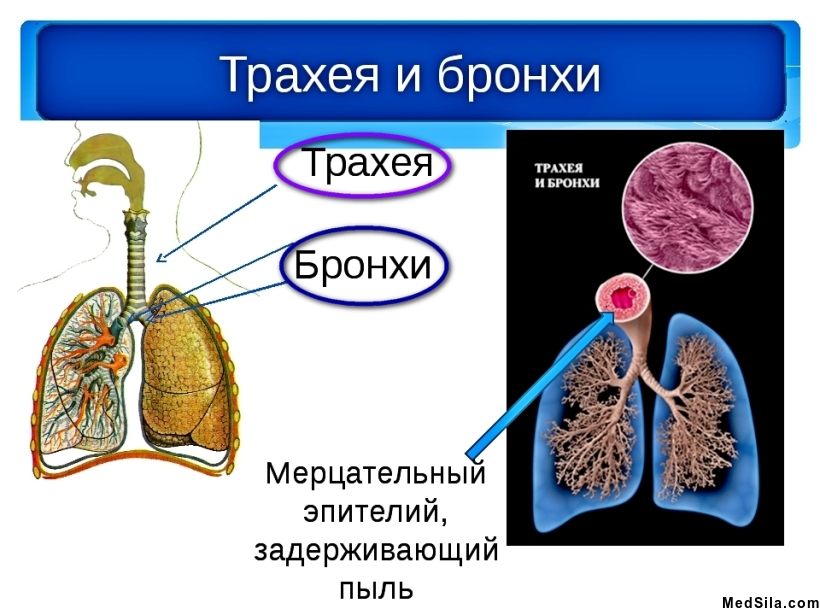

Наши дыхательные пути изнутри выстланы мерцательным эпителием с железами, которые и образуют слизистую оболочку. Слизь, вырабатываемая данной оболочкой, необходима для согревания, очищения и, непосредственно, увлажнения вдыхаемого воздуха, благодаря чему и происходит адекватный газообмен. Если же хоть одна из функций слизистой будет нарушена, возникнут серьезные проблемы, которые неизбежно приведут к различным заболеваниям.

Табак нарушает функцию ресничек мерцательного эпителия слизистой оболочки, что непосредственно ведет к нарушению одной из главных функций слизистой - очищение. Таким образом, легкие «засоряются» и не могут в полном объеме пропускать необходимый кислород. А, как известно, кислород необходимый элемент для жизни человека, и когда его не хватает, человек испытывает постоянную слабость, головные боли, снижение внимания и нарушение мыслительных процессов.

Табачный дым содержит массу ядовитых веществ, которые и оказывают раздражающее действие на слизистую оболочку дыхательных путей, главным образом на трахеи и бронхи. Поэтому в дыхательных путях образуется застойный очаг хронического воспалительного процесса, приводящий к частым простудно-инфекционным заболеваниям, ангинам, бронхитам из-за поражения иммунной системы.